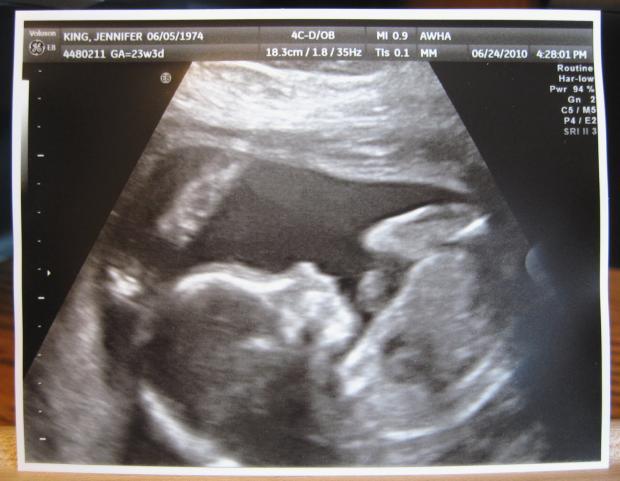

Какие фото УЗИ и живота на 23 неделе беременности? Какой вес и рост плода?

Какие есть фото УЗИ и живота на 23 неделе беременности? Какой вес и рост плода на 23 неделе беременности?

На 23 неделе малыш весит около 450 г и ростом уже 23-25 см. Он похож на большой баклажан или кабачок цуккини. Малыш уже очень похож на человечка, но его кожа еще красного оттенка из-за того, что под ней не сформировалась жировая прослойка. Личико его напоминает старческое и покрыто морщинками. По узи уже точно скажут, кто спрятался в домике — мальчик или девочка, т.к. половые органы закончили свое формирование, а по 3D узи даже можно найти сходство с родителями. На 23 неделе развивается слух и осязание, которое поможет ему найти сосок груди после рождения.